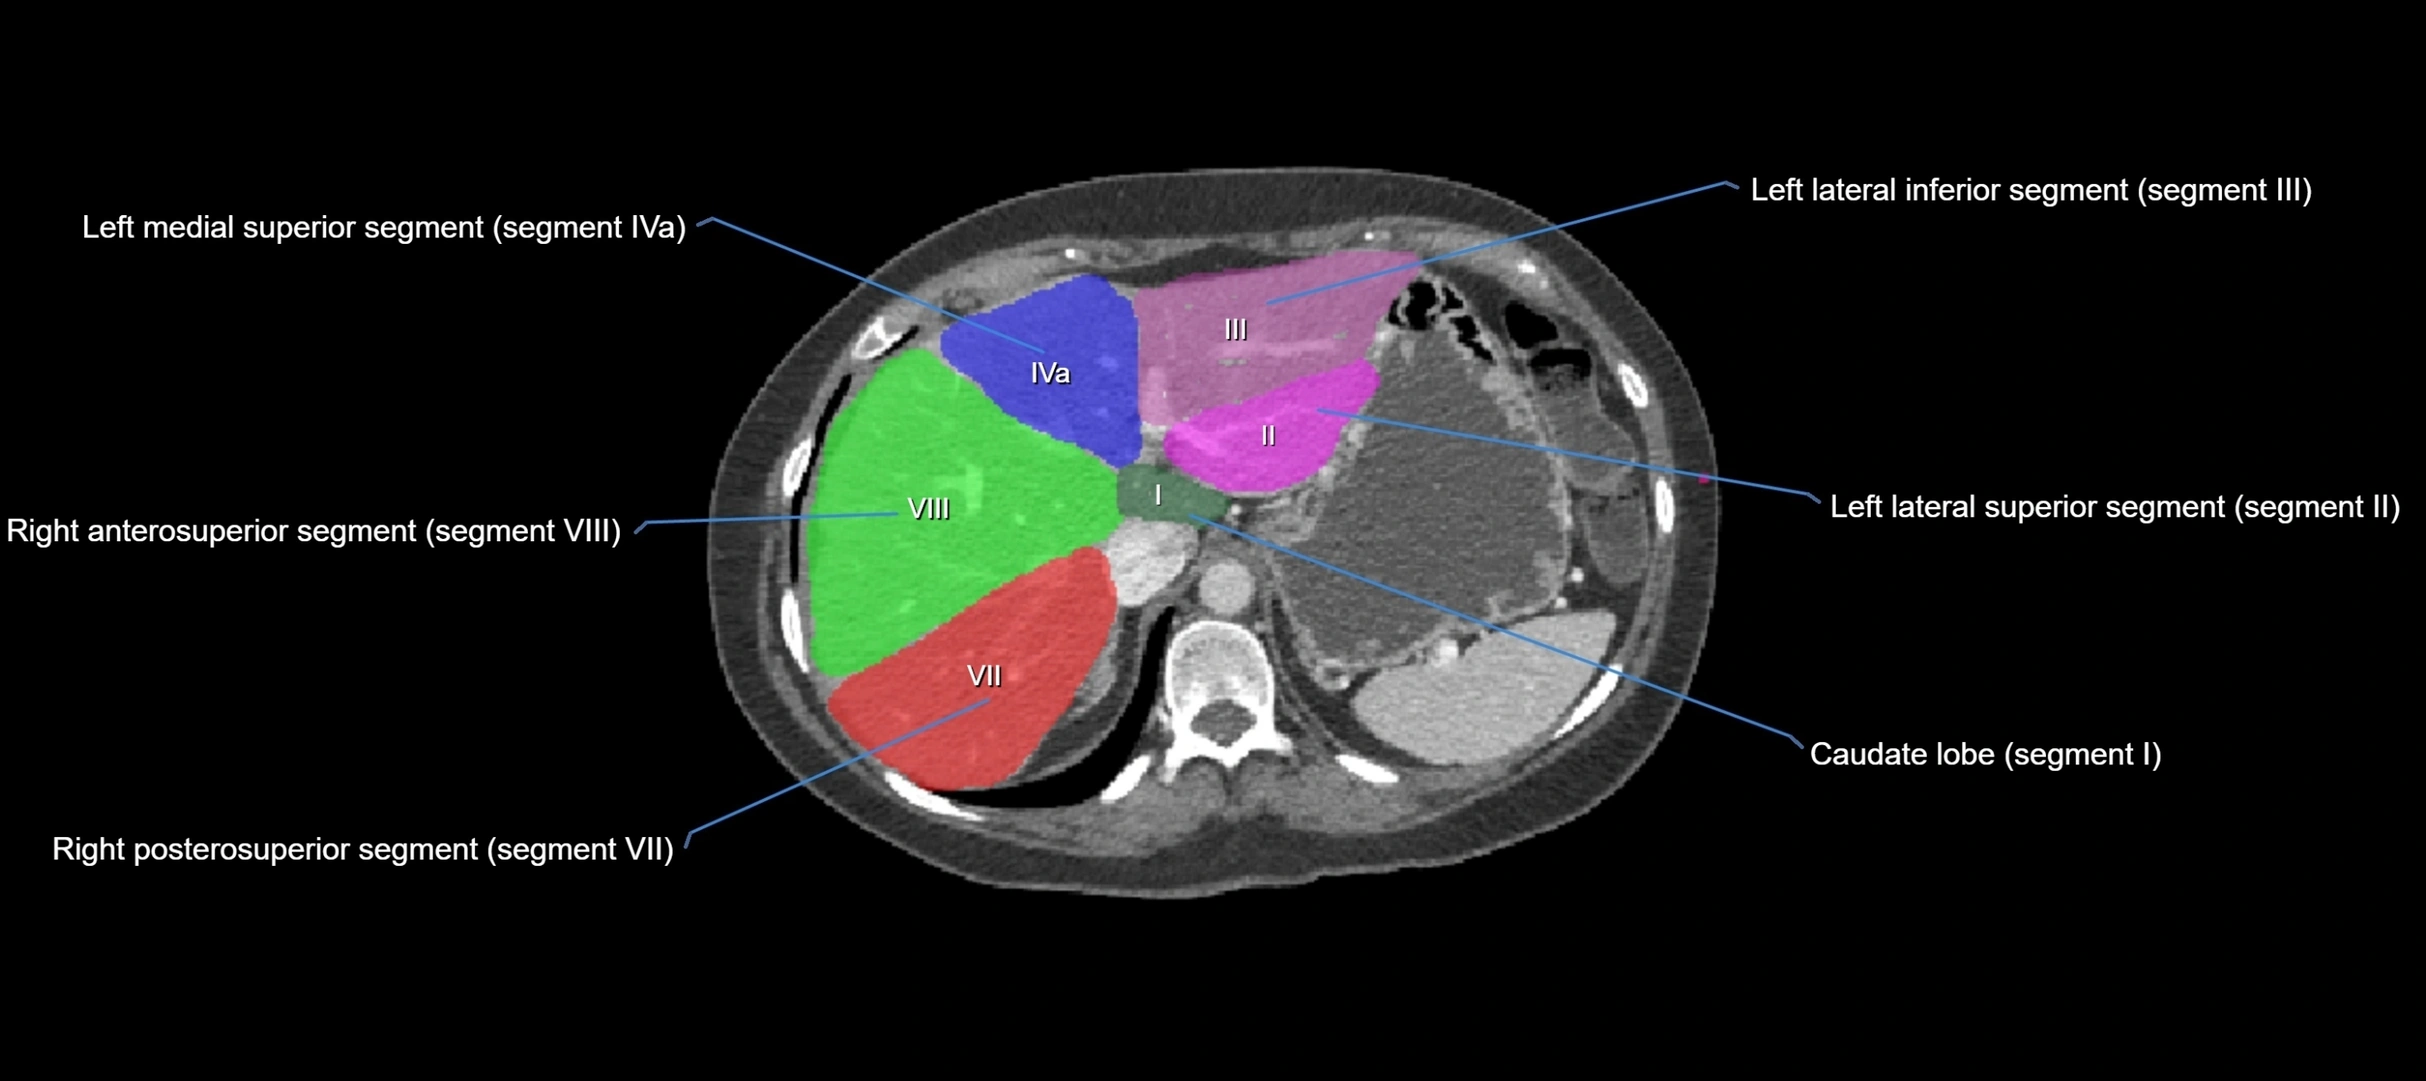

The caudate lobe of the liver is a distinct anatomical subdivision of the liver, designated as segment I in Couinaud’s classification. It lies on the posterior surface of the liver, between the fissure for the ligamentum venosum (left boundary) and the groove for the inferior vena cava (IVC) (right boundary). Superiorly, it is related to the posterior liver surface, and inferiorly it is separated from the left lobe by the porta hepatis.

The caudate lobe is unique because it receives dual portal venous and arterial inflow from both the right and left portal veins and hepatic arteries. It also has independent venous drainage directly into the IVC via multiple small hepatic veins, unlike other lobes that drain through the three main hepatic veins.

This anatomical autonomy makes the caudate lobe especially significant in liver surgery, transplantation, and hepatic venous outflow obstruction syndromes (e.g., Budd–Chiari syndrome). Enlargement of the caudate lobe is a characteristic imaging feature in chronic liver disease and cirrhosis.

CT Appearance

CT Pre-Contrast:

• Caudate lobe appears as a soft-tissue density, isodense to the rest of the liver

• Enlargement may be appreciated in cirrhosis or Budd–Chiari syndrome

CT Post-Contrast:

• Homogeneous enhancement in the portal venous phase, similar to rest of liver

• Independent venous drainage into the IVC may be visualized

• Lesions follow characteristic CT enhancement patterns (HCC: arterial hyperenhancement with washout; hemangiomas: peripheral nodular enhancement with centripetal fill-in)

CT Venous Phase (functional significance):

• Caudate lobe often enhances relatively more than other lobes in Budd–Chiari syndrome, due to preserved venous outflow